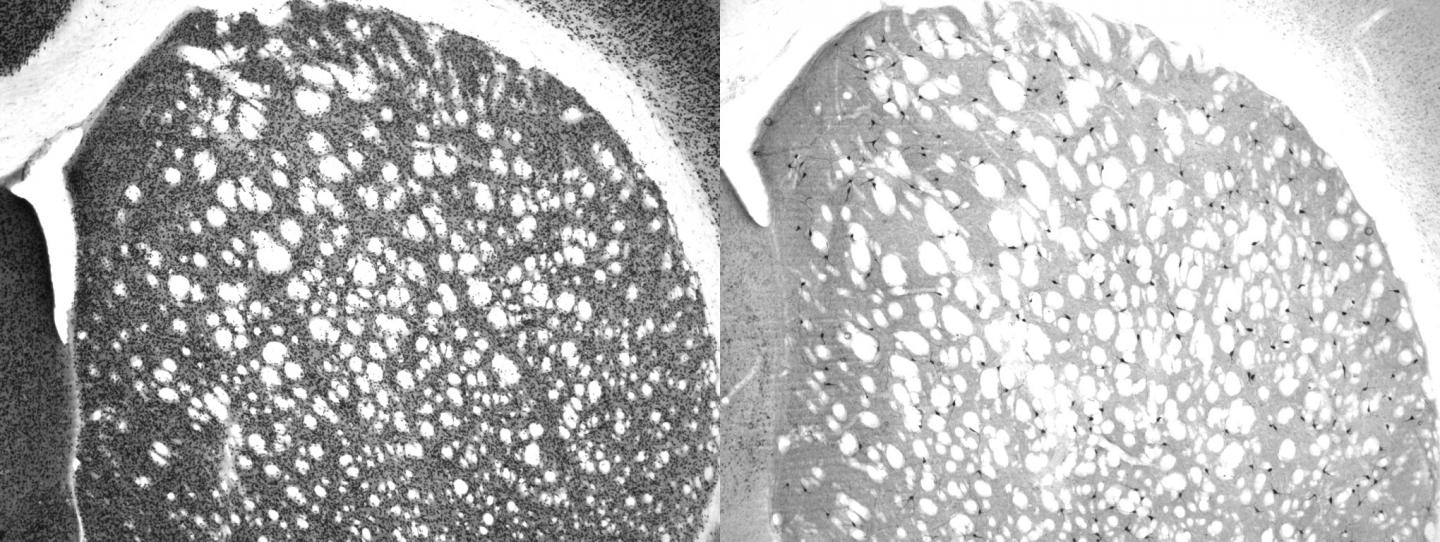

Okinawa, Japan -- Behavioral flexibility -- the ability to change strategy when the rules change -- is controlled by specific neurons in the brain, Researchers at the Okinawa Institute of Science and Technology Graduate University (OIST) have confirmed. Cholinergic interneurons are rare -- they make up just one to two percent of the neurons in the striatum, a key part of the brain involved with higher-level decision-making. Scientists have suspected they play a role in changing strategies, and researchers at OIST recently confirmed this with experiments. Their findings were published in The Journal of Neuroscience.

Previous studies tried to identify the role of cholinergic interneurons by recording brain wave activity during behavioral tasks. While that can strongly indicate specific neurons are correlated with a particular behavior, it is not definitive. In this study, Aoki killed cholinergic interneurons with a toxin that directly targets them, and then observed how rats reacted to rule changes compared with normal rats with intact neurons. "Our experiments show direct causation, not correlation," Aoki said.